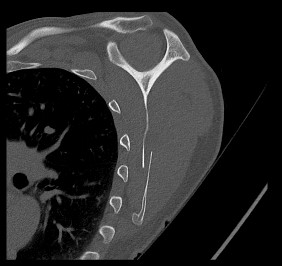

Un homme de 51 ans, en bonne santé, se présente aux urgences suite à une chute à vélo à faible vélocité. Le patient, propulsé par-dessus le guidon, s’est réceptionné sur l’épaule gauche. Il présente une déformation visible de l'omoplate gauche avec limitation douloureuse de la mobilité du membre supérieur gauche, sans déficit neurologique ou vasculaire. L'examen clinique des articulations acromio-claviculaire, gléno-humérale, ainsi que du rachis et du thorax sont sans anomalie.